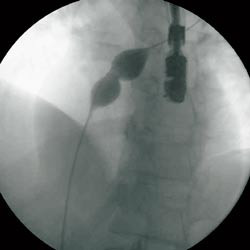

Via en 9 french (F) hylse i høyre v. femoralis, føres et kateter gjennom åpentstående foramen ovale til venstre forkammer og videre til høyre øvre lungevene. Fra denne posisjonen gjøres angiografi for å kartlegge atrienes anatomi. Deretter plasseres et ballongkateter i foramen ovale, og en måler såkalt strukket diameter, som senere brukes til å bestemme paraplystørrelse (fig 2). Ballongkateter og 9 F hylse fjernes og en lang hylse på 11 F føres til venstre forkammer. Pasienten gis heparin 7 500 IE intravenøst. En CardioSEAL paraply (Nitinol Medical Technologies, Boston, USA) (fig 3) lades i et spesielt innføringskateter, slik at de to delene folder seg sammen hver sin vei (fig 4). Paraplyen føres til venstre forkammer hvor den distale delen av paraplyen frigjøres ved at den skyves ut av innføringskateteret. Hele enheten trekkes så mot septum før man løser ut den proksimale del av paraplyen i høyre forkammer. Hele prosedyren foregår under veiledning av transøsofageal ekkokardiografi og gjennomlysning. Ved riktig posisjon står paraplyen sentralt i åpentstående foramen ovale med fire bein hvilende på hver side av atrieseptum og kan frigjøres (fig 5, 6).